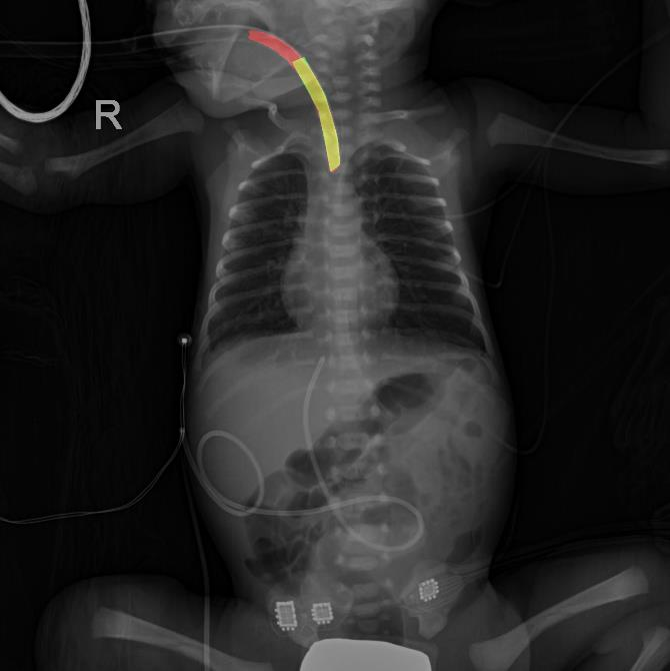

- 모델 출력: 영상과 동일한 크기의 카테터 영역이 표시된 이진 마스크 이미지로, 그 예시는 아래와 같음 (빨간색: 모델 예측 영역, 초록색: 정답 영역, 노란색: 모델이 정답을 맞춘 영역)

ET-tube 분할 결과